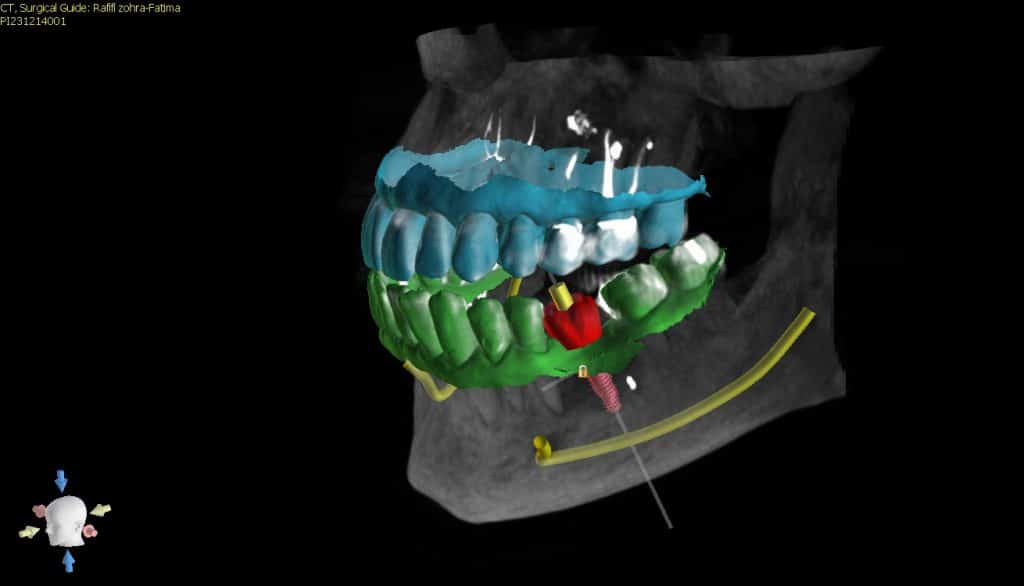

here a guided surgery case where a lower molar was replaces by an implant ,flapless ,thanks to a good digital planification and a realisation of a surgical guide